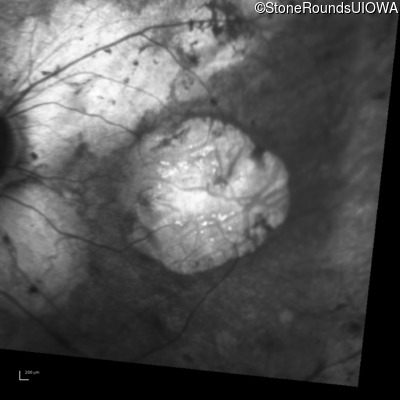

Infrared Fundus Photograph - Right - 20/125 +1

Exemplar